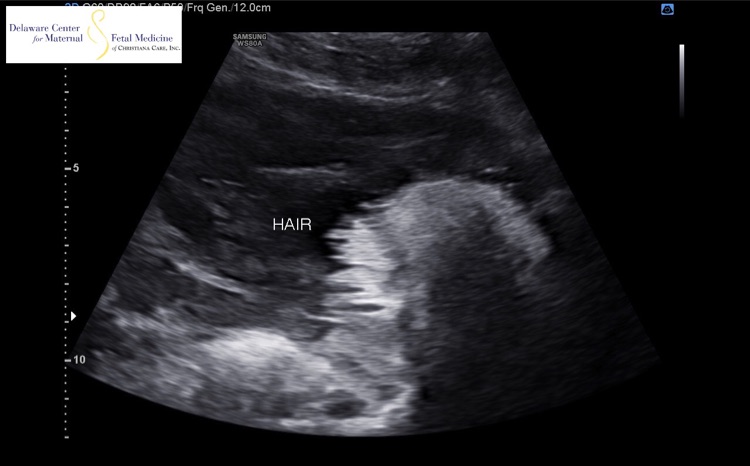

The ultrasound tech told me that the white spiky things is hair and that it looks like he has a lot of it. Has anyone seen hair on the u/s and was it pretty accurate when the baby was born?